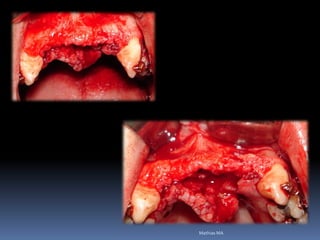

Atrofias ósseas

•Procedimentos de enxertia óssea para

restabelecimento de dimensões perdidas

•Compensações dos tecidos perdidos nas

próteses